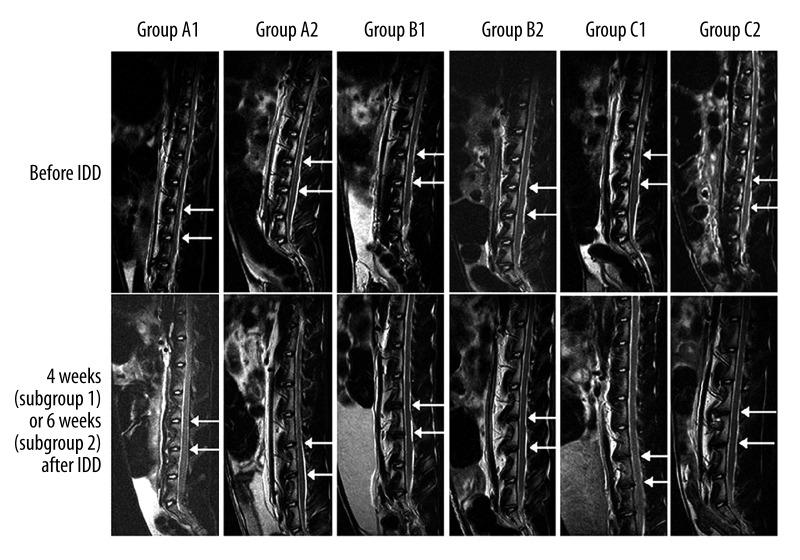

MATERIAL/METHODS: Thirty-six adult New Zealand white rabbits were randomly divided into 3 groups: 0.1 mL PRP (group A), 0.1 mL phosphate-buffered saline (group B), and control (group C) (n=12/group). Annulus fibrosus puncture was performed to establish L4/5 and L5/6 IDD models. Two and 4 weeks later, 6 rabbits from each group were given an IVD injection at L4/5 and L5/6. Two or 4 weeks after injection, rabbits were scanned with X-ray and MRI before being sacrificed. IVDs were collected for hematoxylin and eosin, Masson's trichrome, and Safranin O staining, and type II collagen immunohistochemistry.

Over time, IVD height and disc imaging signal intensity decreased gradually in groups B and C, but only slightly in group A (baseline: 100% for all groups; A: 95.9±4.2% at 4 weeks, 90.1±8.4 at 6 weeks; B: 75.3±5.7% at 4 weeks, 70.8±6.4% at 6 weeks; C: 74.7±5.5% at 4 weeks, 69.9±6.2% at 6 weeks; all P<0.001, P<0.01 between A vs. B and C). Degenerative histological changes in IVDs in groups B and C were more severe compared with group A.